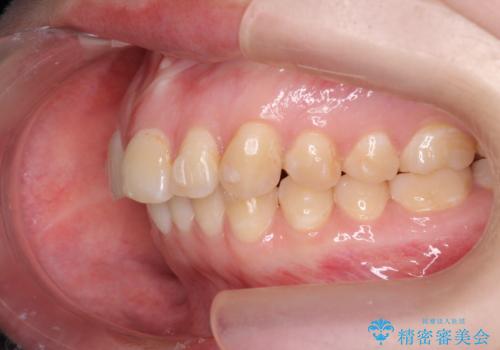

マウスピース矯正で行う出っ歯の治療

- 飛び出したように見える前歯の改善を求めて来院されました。

元々、セラミッククラウンですぐに歯並びを改善したいと希望されていましたが、目立たないマウスピース矯正治療のご提案を行なったところ矯正治療による歯並びの改善を選択されました。

矯正治療を行ったことで出っ歯の改善とともに安定した噛み合わせも手に入れることができました。